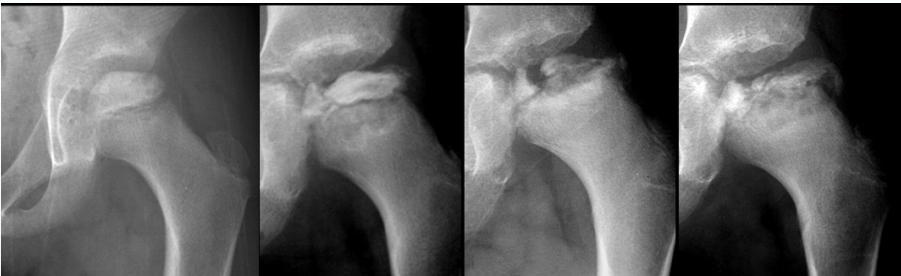

Radiographic Stages:

-

Initial/ Bone Death Stage - May initially appear normal on x-ray

- Increased density followed by collapse

Revascularization and Repair Stage - Reduced density and fragmentation on x-ray

Distortion and Remodeling Stage - Distortion, flattening (coxa plana)

- Enlargement (coxa magna) with partial uncoverage

Radiological Progression:

Progression: Sclerosis → Collapse → Fragmentation → Remodeling

Imaging Examples: